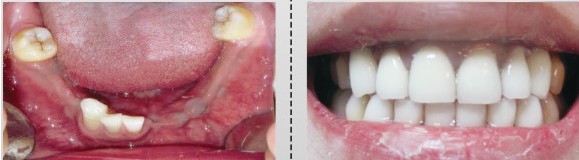

种植牙前后外观对比图